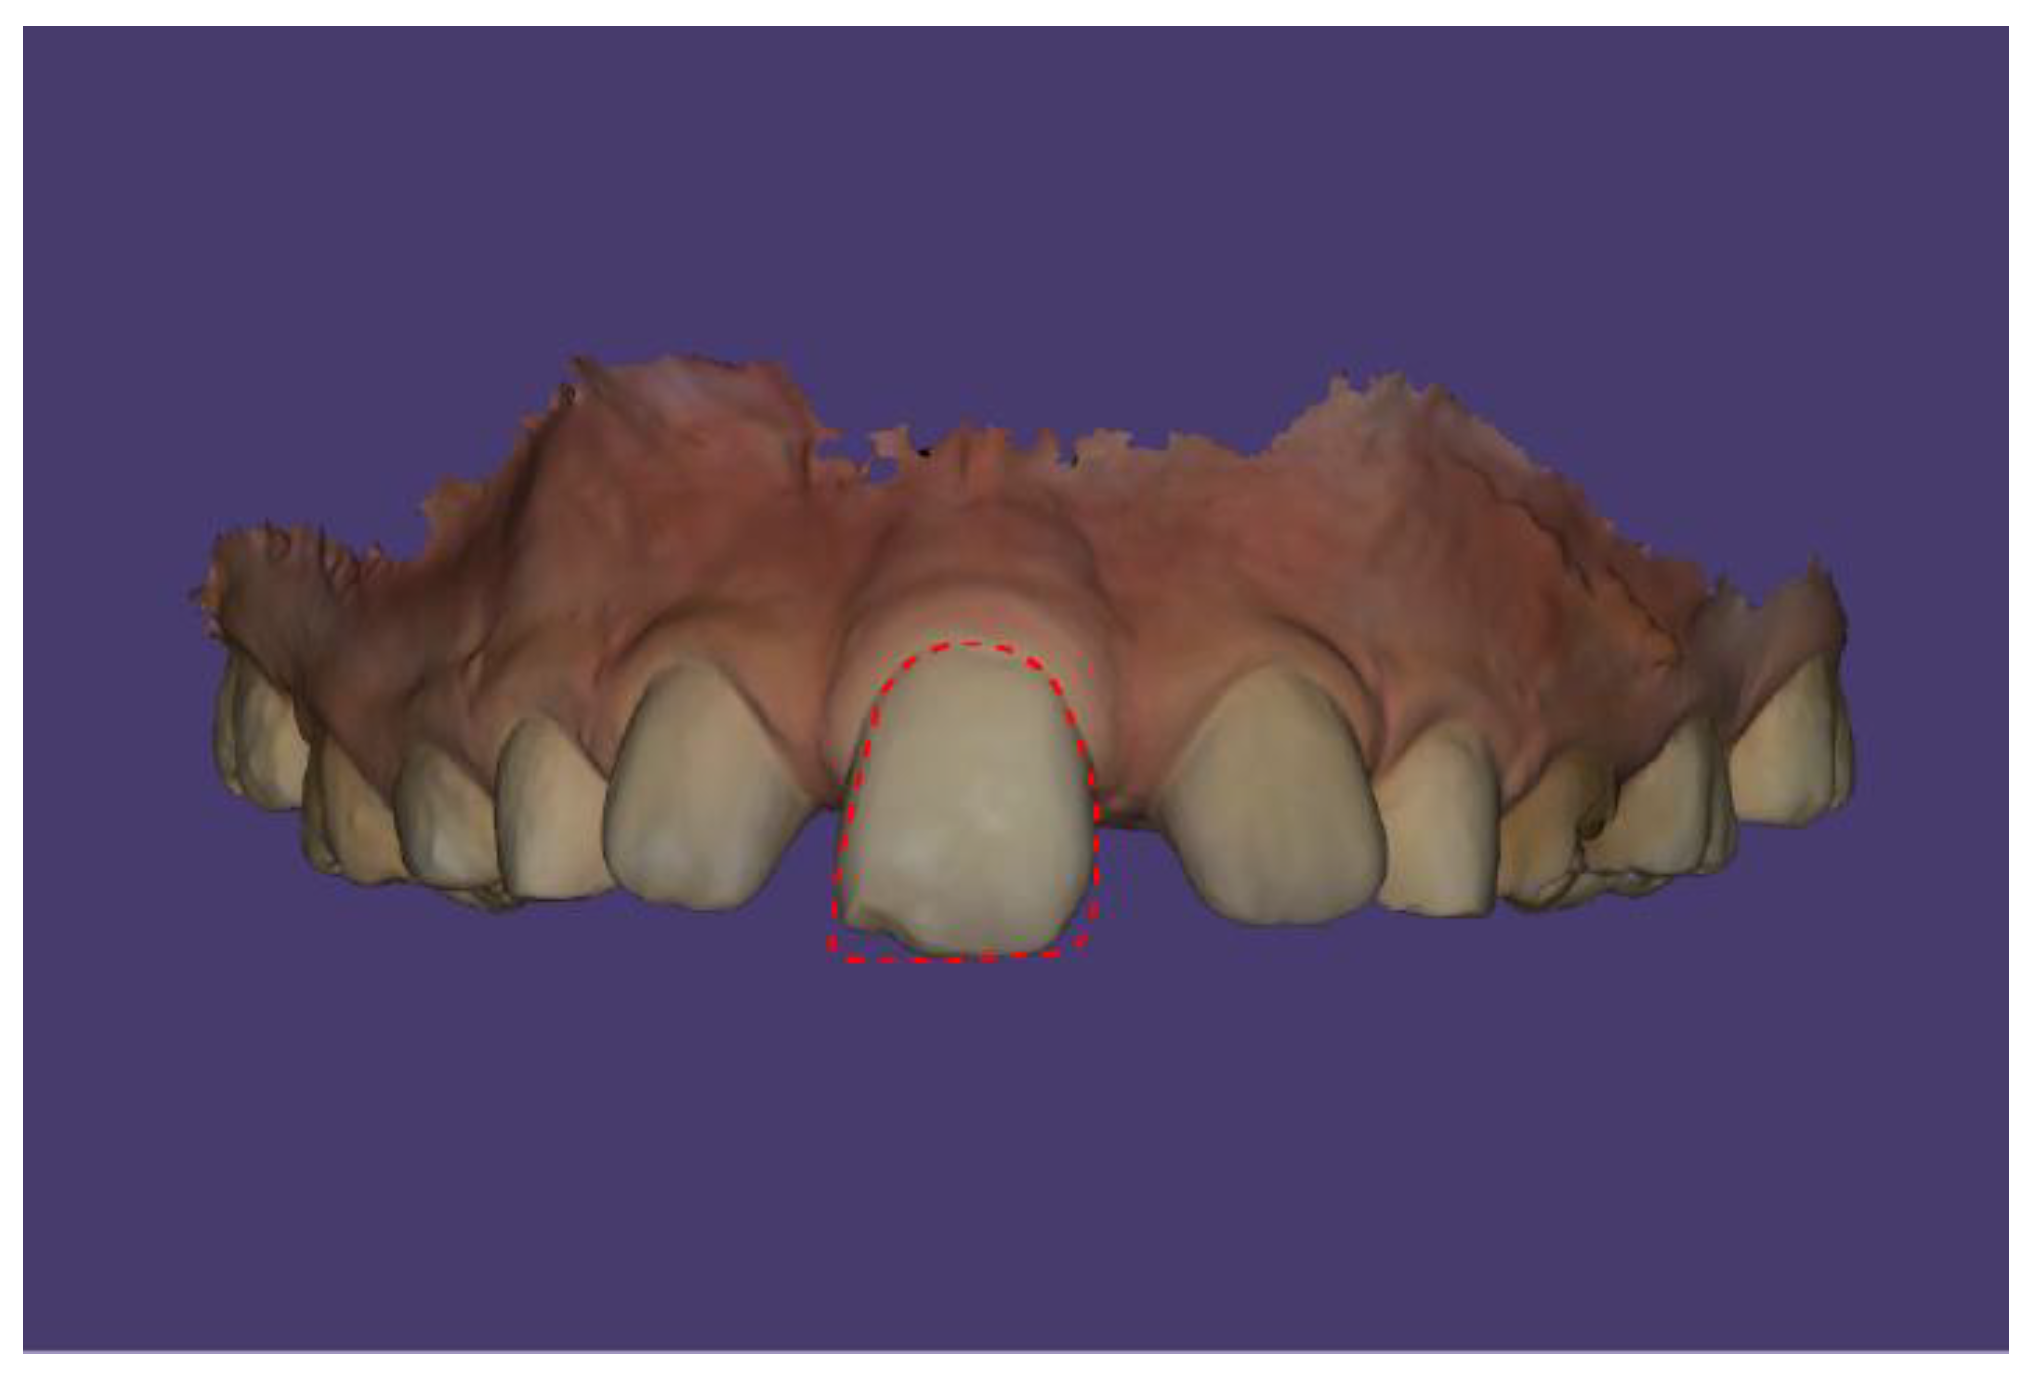

Case Description